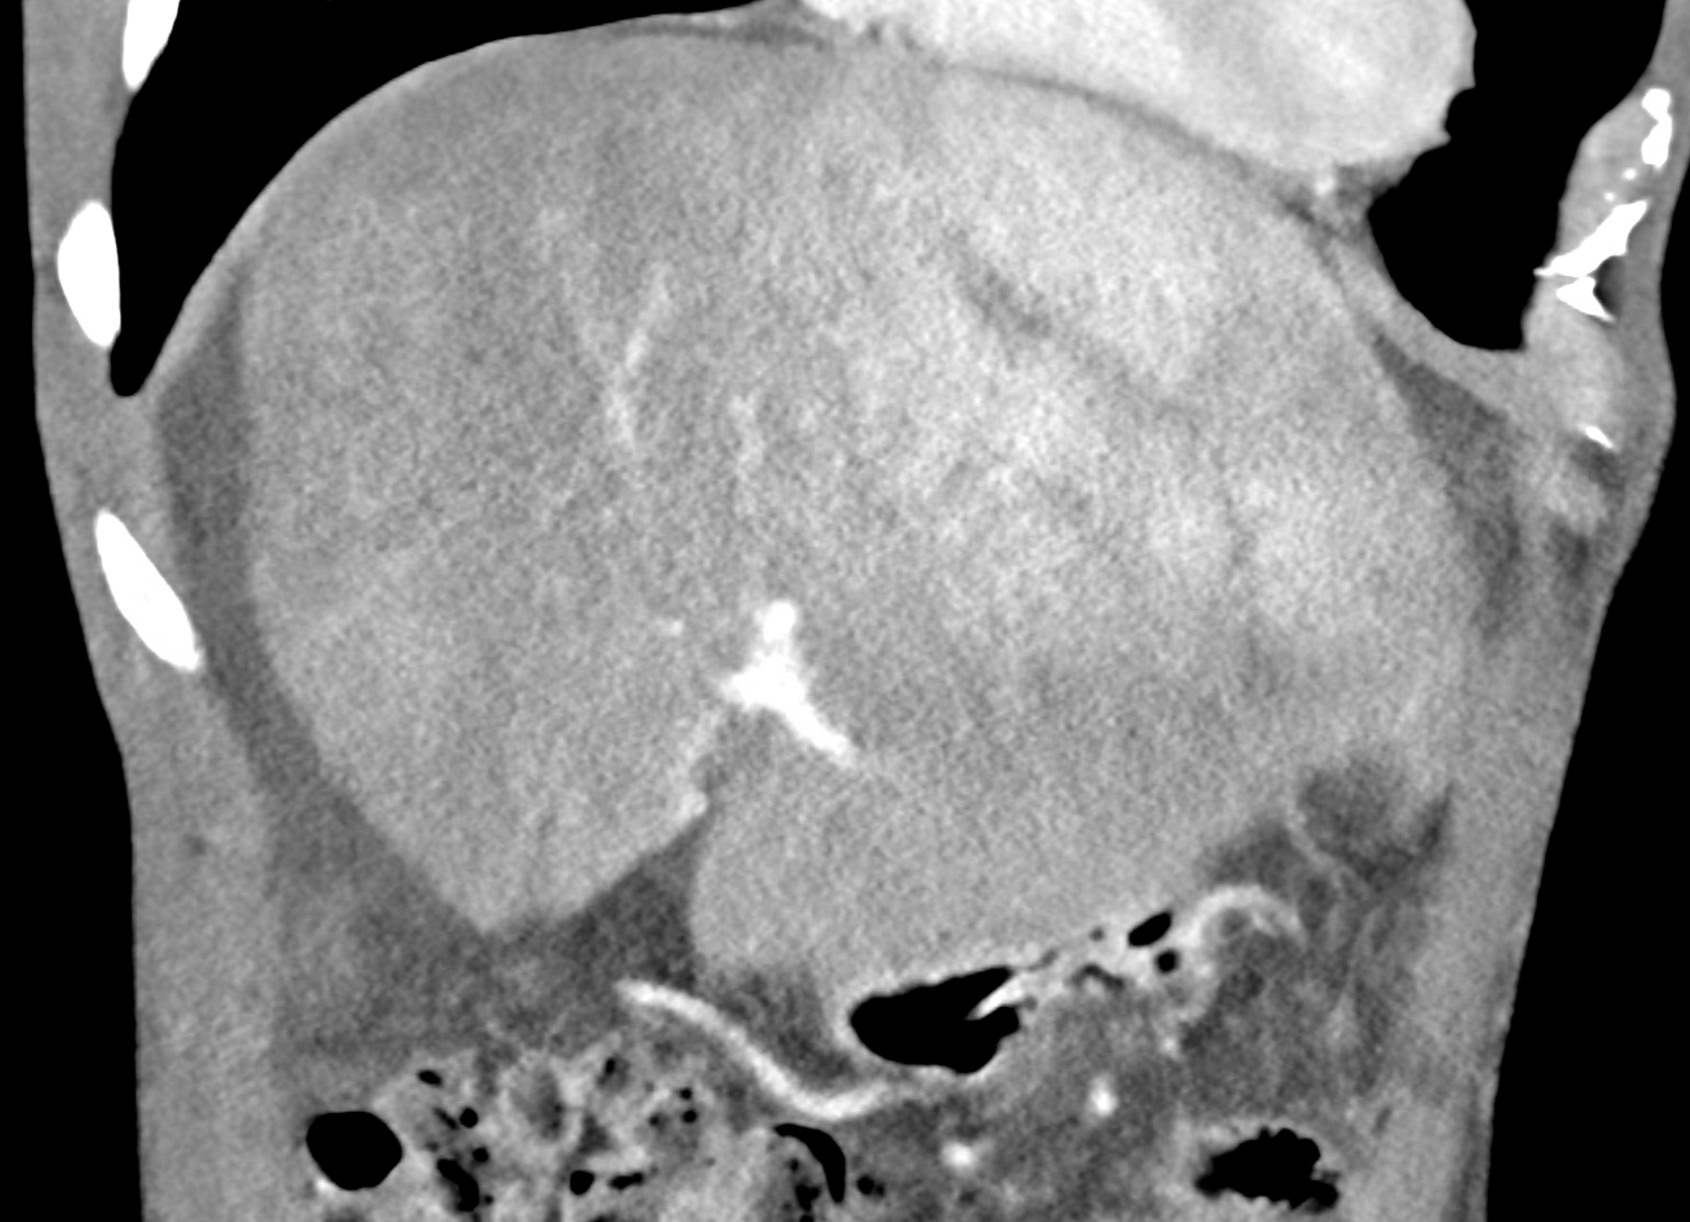

In CT images, BCS manifests as non-homogeneous enhancement of liver tissue in the arterial and especially in the portal phase, although in the portal phase may be increased, especially in the caudate lobe and left lobe, which are often hypertrophic (the hypertrophy and the enhancement is caused due to the possibility of the venous drainage directly into the inferior vena cava through the direct caudate veins), in contrast to the reduction in the right lobe. The portal vein is free, whereas even in the late phase, the hepatic veins and their contrast filling are not visible. Thrombotic occluded veins are hypodense.

A patient in his sixties with a Leiden mutation of factor V and a heterozygous prothrombin mutation presents with abdominal pain. Ultrasound examination reveals ascites and enlargement of the liver.There is enlargement of the liver, particularly the left lobe and caudate lobe. The hepatic veins are centrally filled with contrast medium due to reflux at the confluence with the inferior vena cava, and their radicular parts are thrombosed. There is typical chronic liver remodelling and the formation of centrifugal collateral circulation, including esophageal varices, and ascites is present in the abdominal cavity.

coronary view documenting splenomegaly, different enhancement of the liver parenchyma, and ascites, the arterial, and the portal phases

multiplanar reconstructions showing occluded radices of hepatic veins